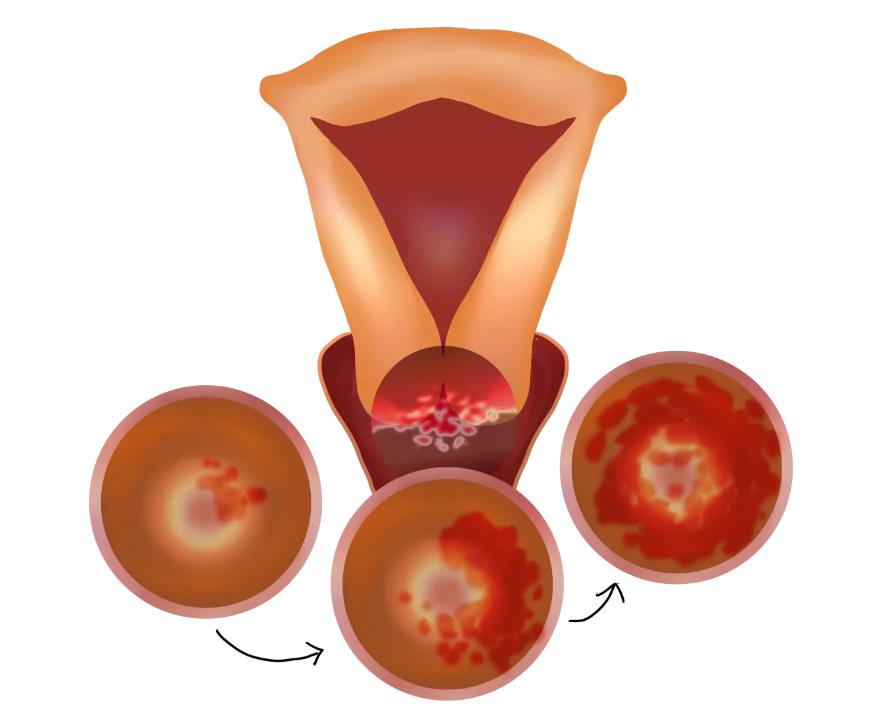

宫颈癌是最常见的妇科恶性肿瘤

99.7%的宫颈癌由HPV病毒感染引起

一旦感染HPV就等于患上宫颈癌(×)

我们知道HPV是导致宫颈癌的重要原因,但并不是说得了HPV就等于患上宫颈癌。

HPV的检测是对宫颈癌筛查的重要补充,HPV阳性往往是宫颈癌的一个主要原因,但是HPV感染的分型很多,有几型很容易得宫颈癌。

HPV病毒就是人乳头瘤病毒,这种病毒大多数在1-2年内会被我们自身的免疫功能清除掉。

如果进行TCT检查正常,建议半年后再复查。只有HPV病毒持续在体内存在,才可能会发展成宫颈癌。